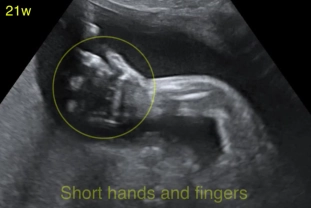

• Loạn sản xương không gây chết

Loạn sản sụn ở trẻ em (Achondroplasia)

• Loạn sản sụn ở trẻ em (Achondroplasia)